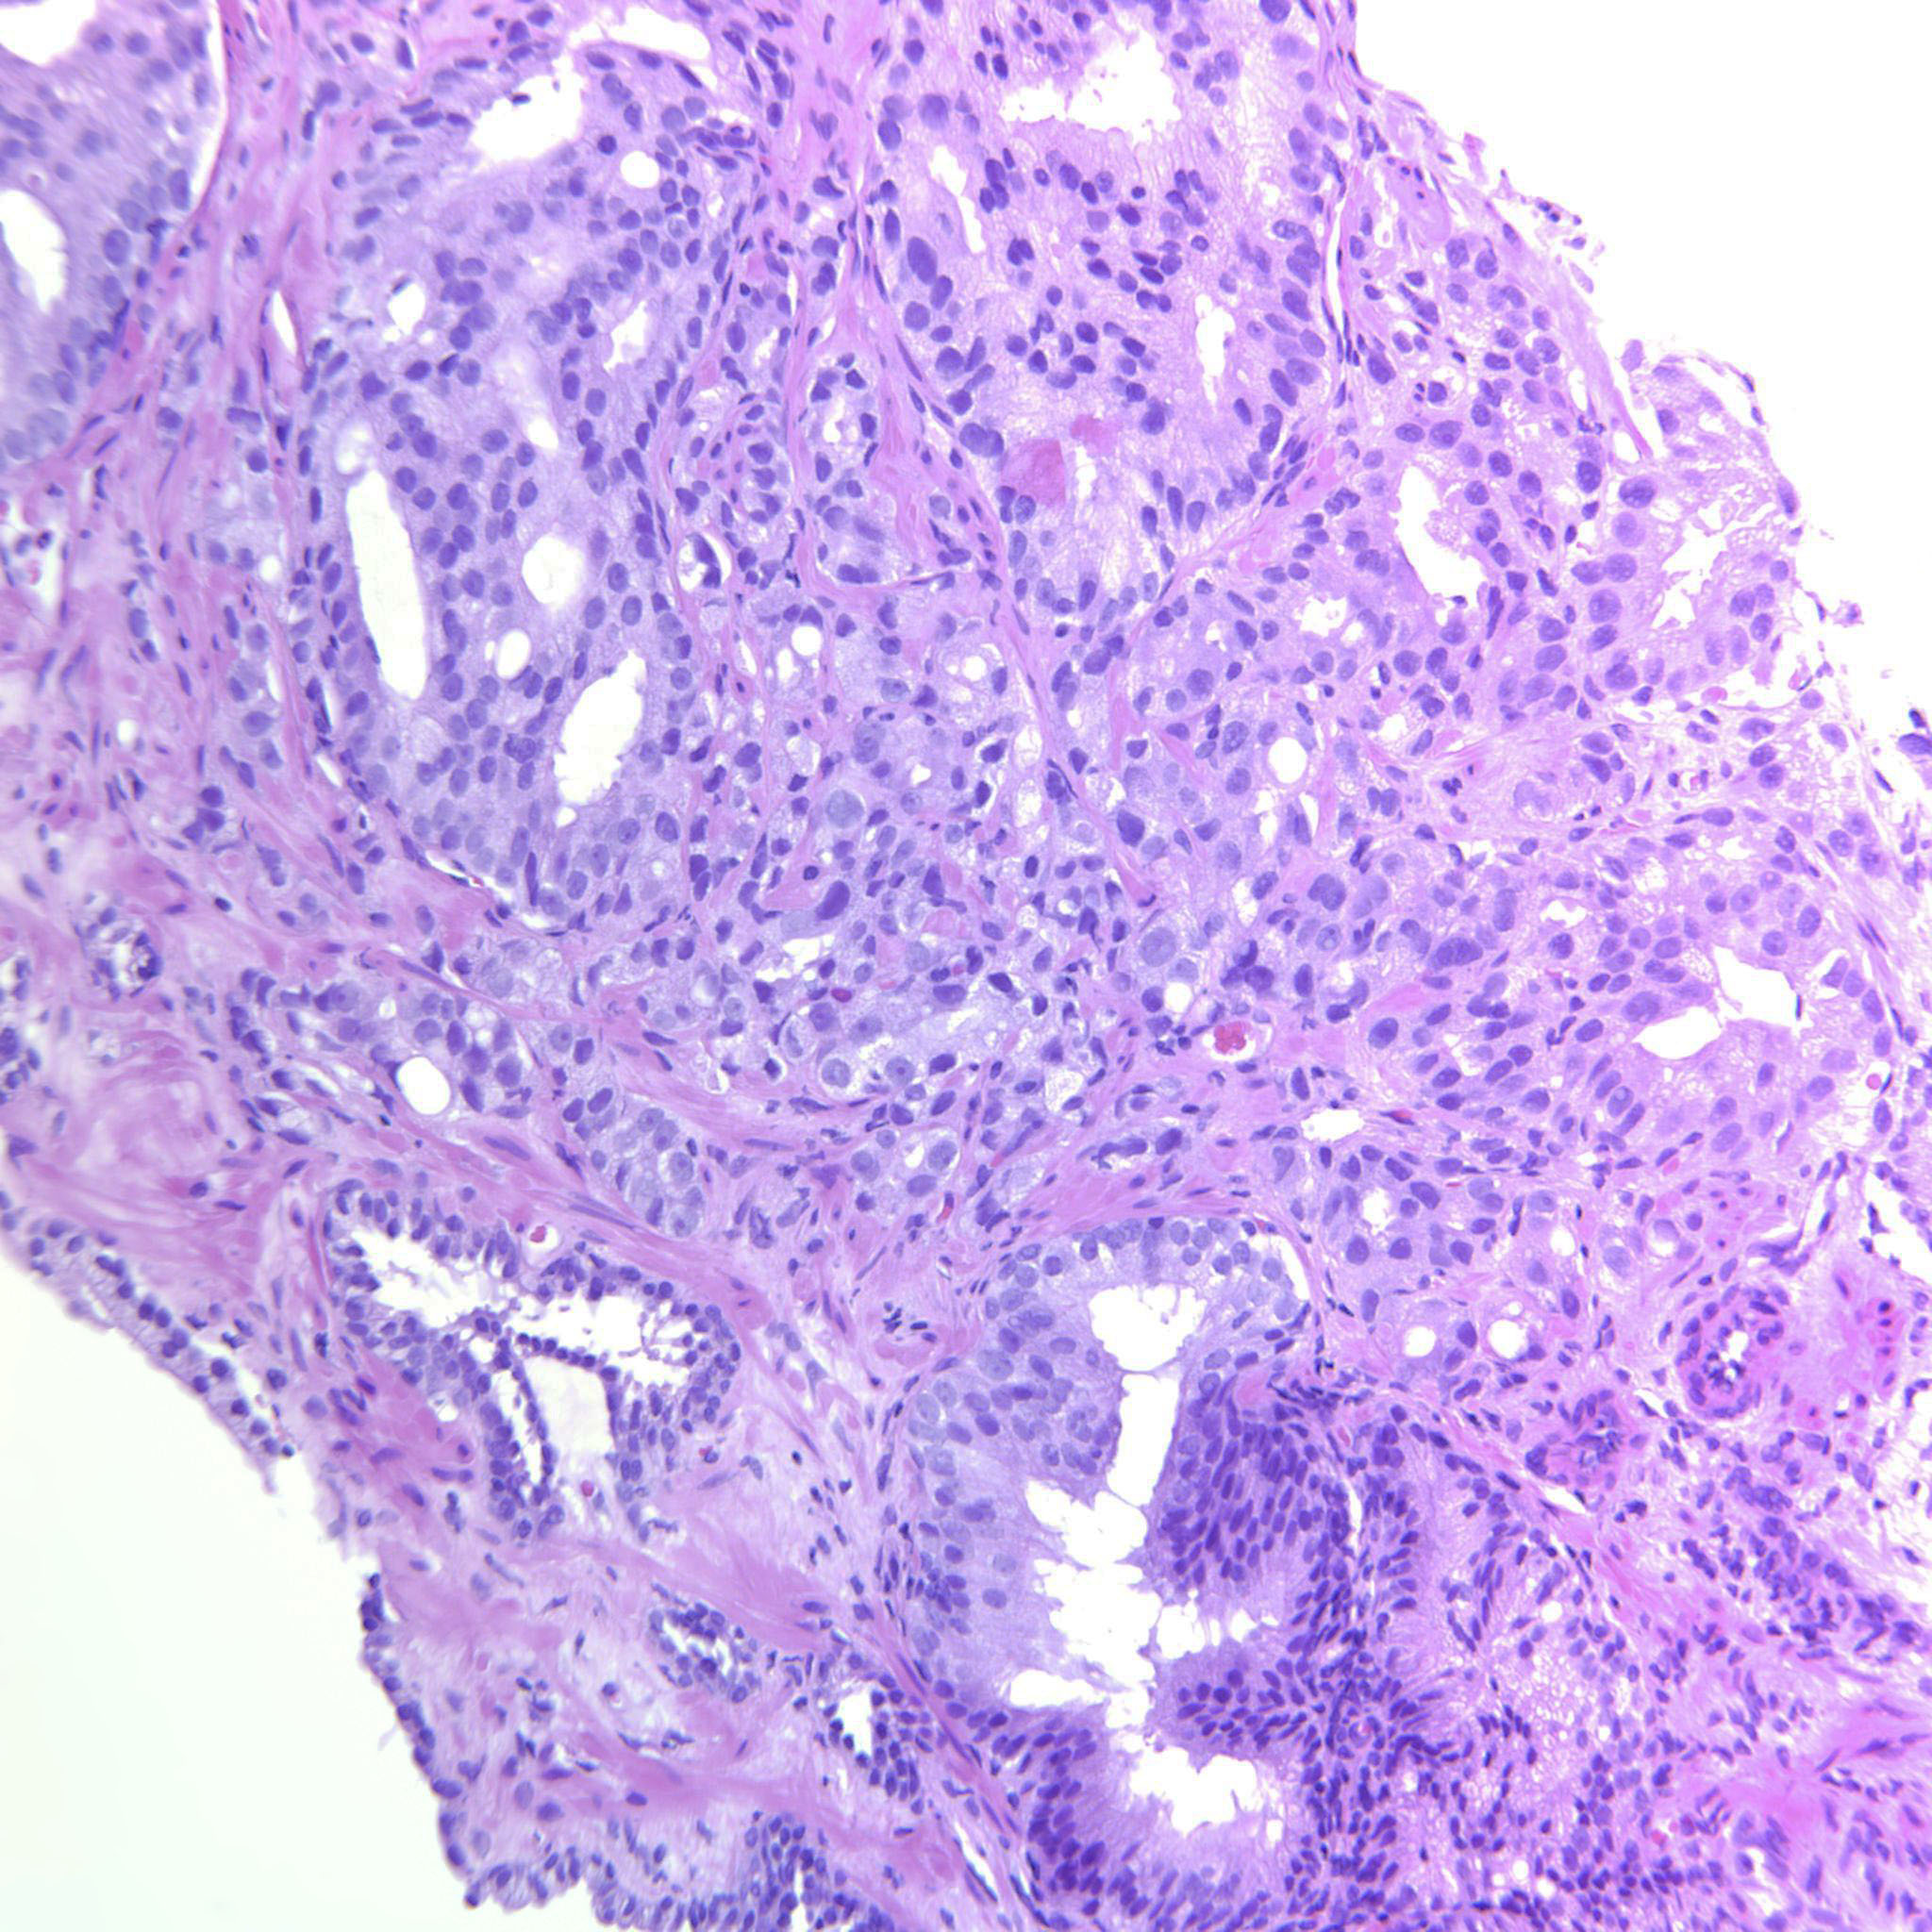

Consensus grade: GS 4+4=8 (ISUP 4)

Case description (by case creator):

Large cribriform sheets and also tightly packed poorly formed glands. Some seem to be solid nests or single cells but not convincing for GP5.